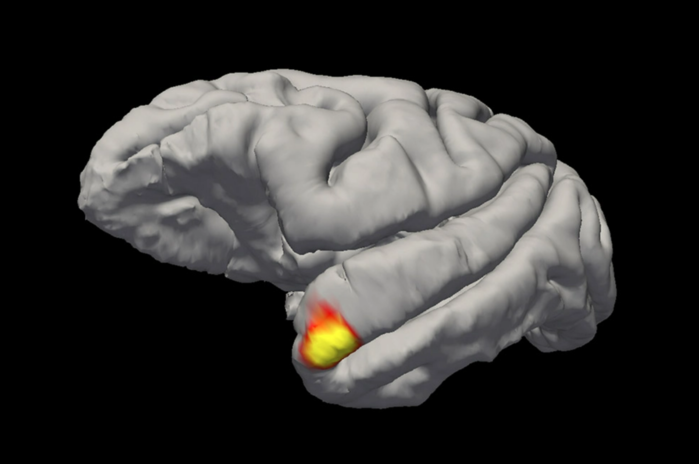

|

| ▲ "할머니 뉴런"은 측두엽의 정점에 위치한다. © Sofia Landi |

하지만 랜디와 그의 연구팀이 발견했듯이, 우리에게 매우 친숙한 얼굴, 즉 할머니, 부모님, 또는 친한 친구의 얼굴의 경우, 지름길이 있는 것으로 보인다. 측두극의 뉴런들은 기억을 먼저 참조하지 않고도 그러한 얼굴을 인식한다. 이 뉴런들은 특정 얼굴에 대한 기억을 저장해 두었다. 랜디는 "한편으로 이 세포들은 감각적이고 시각적이지만, 다른 한편으로는 기억 세포처럼 기능한다"고 설명했다. 흥미롭게도, 이러한 빠른 인식은 우리가 잘 알고 직접 만난 사람에게만 효과가 있다. 화면에서만 본 얼굴에는 효과가 없다.